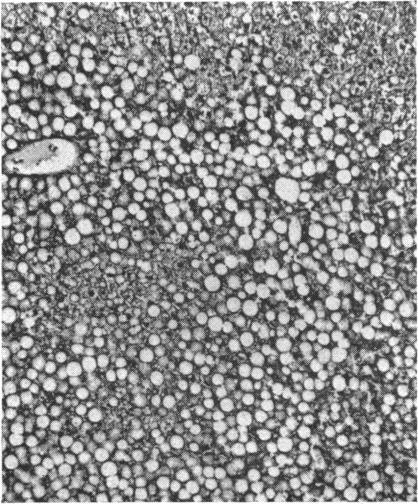

The relation between ammonia intoxication and liver disease is not clear. Ammonia appears to be relatively non-toxic to normal individuals, whereas some patients with liver disease appear to be exquisitely sensitive to dietary protein, ammonia-releasing substances, and ammonium salts. In an attempt to elucidate this relationship the intravenous LD(50) of ammonium chloride was determined in both normal mice and in those with liver disease produced by a variety of means. Parenchymal damage was created by acute and chronic carbon tetrachloride intoxication, a low-protein, lipotrope-deficient diet, and mouse hepatitis virus. Mice in which the portal vein had been partially ligated and those infected with Schistosoma mansoni developed portal-systemic collateral circulation. Groups of these mice were placed on high-protein diets and ammonia drinking water for periods as long as two months. A combination of both parenchymal damage and collateral circulation was induced in mice either by bile duct ligation or by a combination of schistosomiasis and acute carbon tetrachloride intoxication. When the above groups of mice with liver disease were compared with normal control mice in the same weight range, the LD(50) of ammonium chloride showed no striking change.

氨中毒与肝脏疾病之间的关系尚不清楚。氨对正常个体似乎相对无毒,而一些肝病患者似乎对膳食蛋白质、氨释放物质和铵盐极为敏感。为了阐明这种关系,测定了正常小鼠以及通过多种方式诱发肝病的小鼠静脉注射氯化铵的半数致死量(LD50)。通过急性和慢性四氯化碳中毒、低蛋白、缺乏促脂物质的饮食以及小鼠肝炎病毒造成实质损伤。门静脉部分结扎的小鼠以及感染曼氏血吸虫的小鼠形成了门体侧支循环。将这些小鼠分组,给予高蛋白饮食并饮用含氨的水,持续长达两个月。通过胆管结扎或血吸虫病与急性四氯化碳中毒相结合的方式,在小鼠中诱导实质损伤和侧支循环同时出现。当将上述患有肝病的小鼠组与相同体重范围的正常对照小鼠进行比较时,氯化铵的LD50没有显著变化。